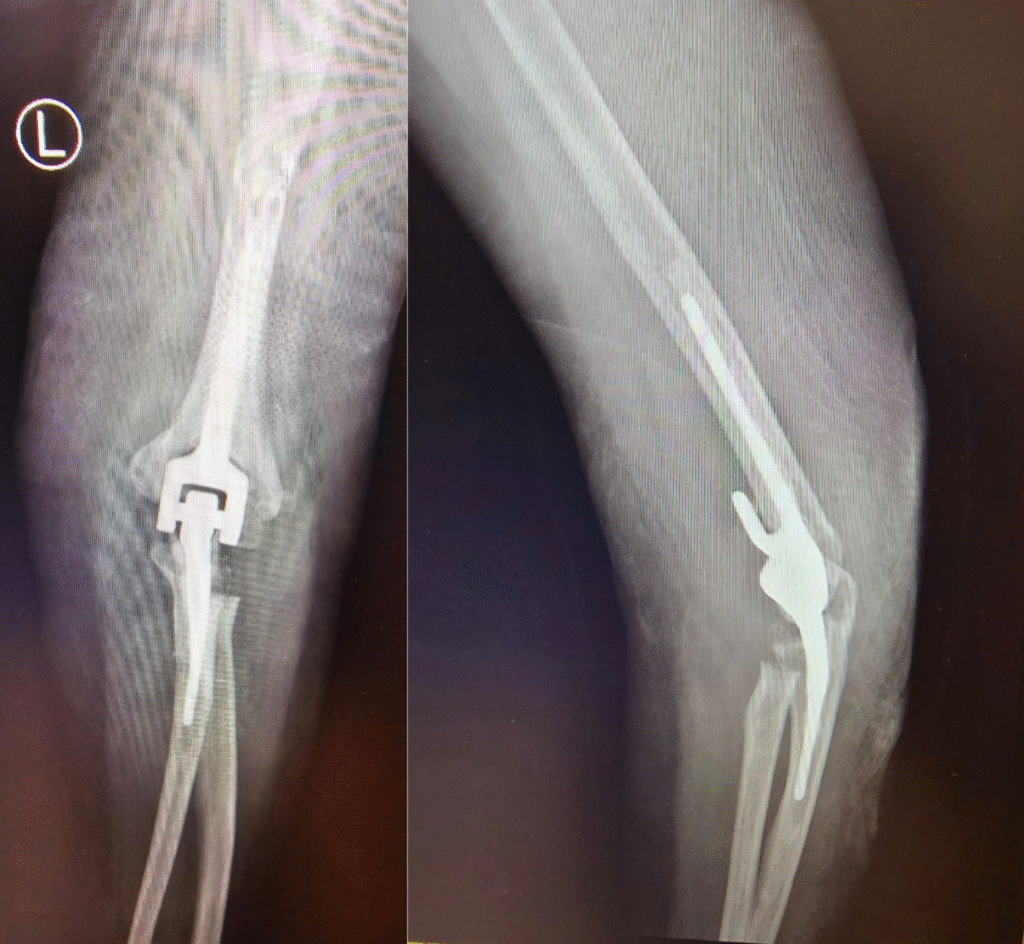

Total Elbow Replacement

This 50 yr old lady had Rheumatoid Arthritis with painful and swollen both elbows with restricted ROM. Did a Total Elbow Replacement on the left side with good ROM.